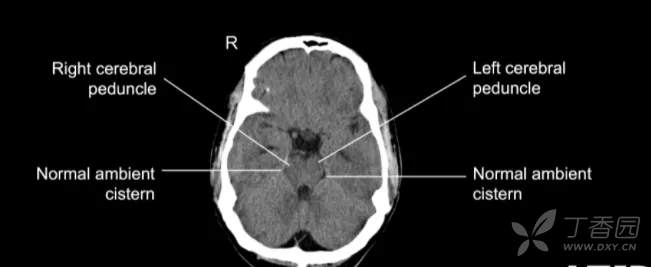

环池

环池 ambience cistern 分本部和翼部。

环池本部围绕中脑大脑脚两侧,连接于四叠体池和脚间池之间。

翼部向外伸向丘枕后下方,又名丘脑后池。

环池内有大脑后动脉、小脑上动脉、脉络丛前动脉和后动脉、基底静脉和滑车神经。

由四叠体池、环池和脚间池可勾画出中脑的轮廓。